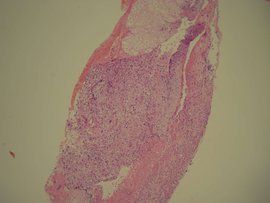

病理診斷

賁門息肉組織類型分:鱗狀增生、 腺瘤型增生、炎症型、潰瘍型、糜爛型、上皮 非典型增生型,(分三度:輕度—中度---重度),中、重度增生有癌變可能。